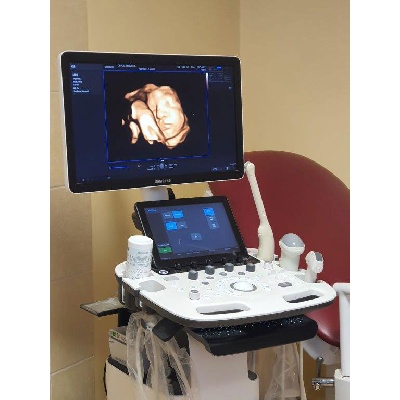

Használt Samsung HS50 típusú 2D/ 3D/ 4D/ 5D ultrahang készülék két vizsgálófejjel

| Gyártó: | SAMSUNG MEDISON |

|---|---|

| Pontos típus: | USS-HS5NL3M/WR |

| Gyártás éve: | 2021 |

| Irányár (bruttó): | 7.800.000,- Ft |

| Műszaki állapot: | Újszerű |